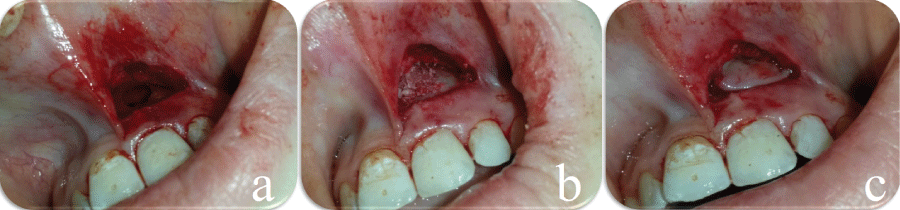

This report describes four female patients presented with (lateral cyst on tooth 22; periimplantitis on mandibular left first premolar area; furcation lesion on tooth 36, periapical abcess on teeth 11-21) (Table 1). All patients were informed about the treatment procedures, and were required to fill out a consent form and a medical history questionnaire. The current article was conducted in full accordance with the World Medical Association Declaration of Helsinki. Before the surgical procedures, patients were underwent oral hygiene instructions and scaling with ultrasonic and hand instruments to remove any local irritating factors that may have been responsible for the gingival inflammation at the surgical wound healing duration. In the surgery processes, mucoperiosteal full-thickness flaps were elevated to perform the surgical debridement of lesion areas in all patients under local anesthesia (articain 4% with 1:200.000 epinephrine†). 10 cc venous blood was taken to prepare 2 pieces of CGF with special centrifuge‡. One piece was mixed with 0.25-0.5 gr сancellous-cortical heterologous bone mix§ to accelerate new bone formation and the other was used as a barrier membrane. After complete removal of granulation tissue at lesion areas, minced CGF mixed with bone graft was gently tapped inside the osteotomy site with osteotomes and mallet to fill the defects. CGF barrier was covered on the graft to accelerate new bone formation and prevent soft tissue ingrowth (Figure 1). After repositioning the soft tissues, primary closure was attained using 4-0 silk suture. Analgesics and antibiotics were prescribed, and the patient was advised to use chlorhexidine mouthwash for a week.

Figure 1: a) Intra-oral view of the lesion after removal of granulation tissue; b) Applying CGF mixed with bone graft; c) CGF barrier membrane.